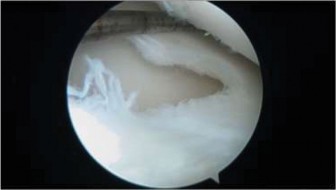

Figure 10–32

Discussion

The correct answer is (C). The arthroscopic images demonstrate a complete discoid meniscus which is covering the entire lateral tibial plateau. As the patient is symptomatic from the meniscus, saucerization is the first step in management. The meniscus is trimmed back using a combination of shavers and biters to a stable peripheral rim, which replicates the width of the native meniscus. Complete meniscectomy would not be indicated in a patient of this age due to the high risk of early onset degenerative arthritis. In fact, even prior to intervention, many discoid menisci have been associated with the development of lateral hemijoint osteochondral lesions. Although chondroplasty may be necessary, the meniscus is the underlying problem causing chondral wear and must be dealt with first. After saucerization is performed, the meniscus is probed and the following arthroscopic image is seen (Fig. 10–33). The next step in management is: